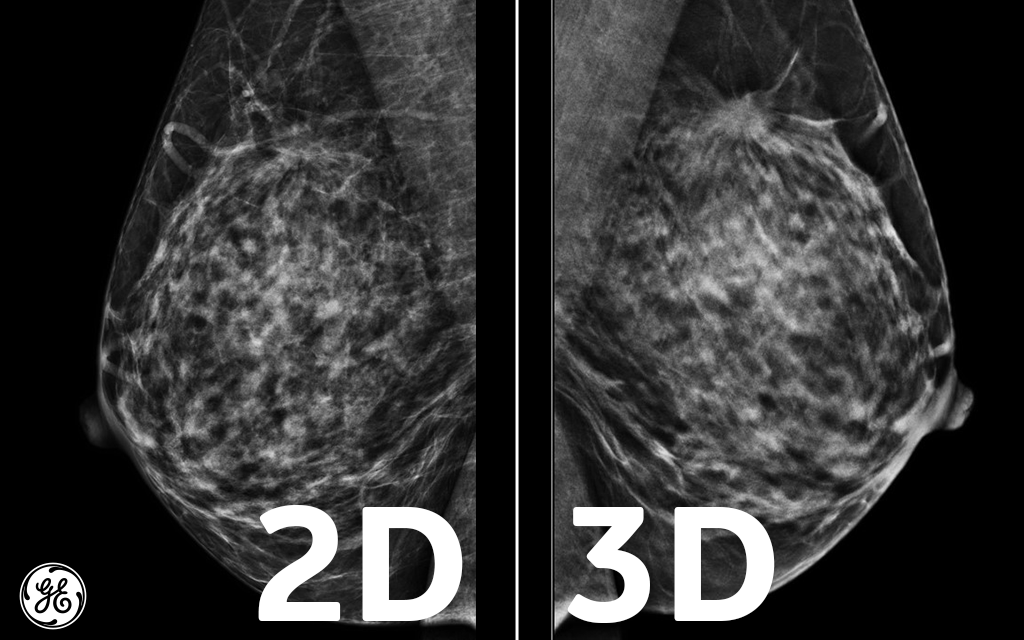

Dense breast tissue appears solid. Essentially, mammograms turn a 3d object into a 2d object. Finding breast lumps and seeing change in the size and shape. Ultimately, the news is good: A number of studies have found that 3d mammograms find more cancers than traditional 2d mammograms and also reduce the number of false positives. A mammogram can show breast changes such as calcifications, masses, or other symptoms that might be cancer. Calcifications are calcium deposits within the breast tissue and they look like small white spots. Digital breast tomosynthesis (tomo), also known as 3d mammography, is a revolutionary new screening and diagnostic breast imaging tool to improve the early detection of breast cancer. American cancer society, 9 oct 2017. Ultrasound characterization of breast masses. indian journal of radiology and imaging. However, when the breast is compressed from top to bottom, the tissue in the upper breast can overlap tissue in the lower breast. Any area that does not look like normal tissue is a possible cause for concern. It appears to be developing in a concentric pattern.

What does breast cancer look like on a mammogram? Screening mammograms have been used since the 1980s. On mammograms, dense breast tissue looks white. Bright spots on a mammogram that look like potential tumors could turn out to be overlapping tissues or a blood vessel folding over on itself, friedewald said. The outer edges of these cells look fuzzy or spiky (called spiculated). Moose & doc breast cancer, 21 may 2018. It is also an anatomic test, which means cancer is detected based on changes in how the breast anatomy looks. Food and drug administration in 2011. After a mammogram that didn't show anything, and a sonogram that found the lump, i was diagnosed with stage 2 breast cancer. Treatment typically involves some type of surgery and depends upon the staging of the. What does breast cancer look like on a mammogram? It appears to be developing in a concentric pattern. A mammogram can show breast changes such as calcifications, masses, or other symptoms that might be cancer.